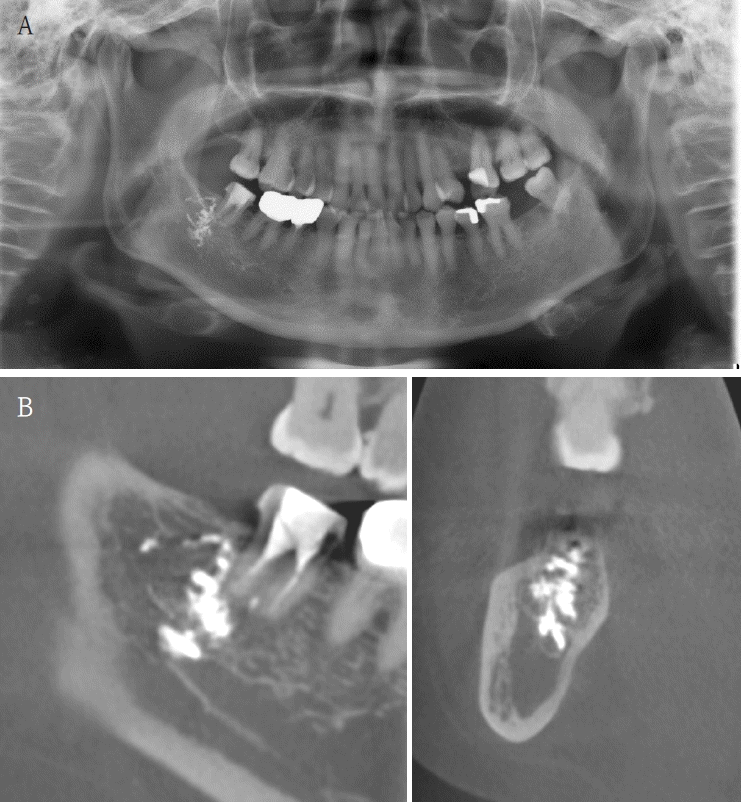

A 63-year-old female presented three days after endodontic treatment of the mandibular left second molar (#37) with symptoms of numbness in the left lower lip and gingiva. A panoramic radiograph and cone-beam computed tomography (CBCT) revealed extrusion of Calcipex II into the mandibular canal (Fig. 1). Initial neurosensory testing demonstrated mild hypoesthesia. She was admitted for foreign body removal and neurorrhaphy under general anesthesia. A post-operative panoramic radiograph confirmed the removal of the foreign body (Fig. 2). Although surgical curettage and neurorrhaphy were performed on the fourth day post-onset, no significant symptom relief was noted at the one- and two-week follow-ups. At the three-month follow-up, she reported persistent numbness with mild neuropathic discomfort but no marked improvement. A follow-up neurosensory exam is scheduled for the six-month check-up.- Case 2